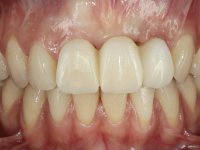

In the initial phase, it was proposed to the patient to perform the surgical implant exposure and after clinical evaluation, make prosthetic decisions. Once the healing screw was placed and the soft tissues were healed, an inadequate position of the implant was found. In view of the dramatic situation, the patient was proposed to remove the implant and put a new one after tissue regeneration. This proposal was rejected by the patient, who suggested temporary rehabilitation of the current implant. A new proposal was then made, to rehabilitate the implant, consisting of a screwed abutment, and on this, the placement of an acrylic crown with coronal and gingival components. After 6 years with the provisional treatment, the patient appeared in consultation with an abscess in tooth 1.1. After clinical and imaging analysis, it was decided to remove teeth 1.1 and 2.2, submerge the implant, place two implants at the site of 1.1 and 2.2 and perform adequate tissue regeneration. Temporization would be done with a provisional 3-element bridge, adhered with a net to the neighboring teeth. After osseointegration, definitive rehabilitation would be done with a 3-element bridge, including zirconia infrastructure and ceramic cover.

The surgical implant exposure and the healing screw placement proved to be a negative surprise regarding its position. Since the proposed removal of the implant was refused, we advanced to its provisional rehabilitation. An open tray impression technique was done, and a screwed abutment with a coronal and gingival component and an acrylic crown were made in the laboratory, using these two components. The provisional crown was placed in the mouth until a final decision was made. Six years passed before the patient returned to the clinic with an abscess on tooth 1.1. The choice to remove teeth 1.1 and 2.2 was made, to create a provisional 3-element bridge with a net to be adhered to the adjacent teeth. Surgery was planned and performed, placing the two implants at the site of 1.1 and 2.2, and the implant at the 2.1 site was cut with the objective of submerging it, while adequate tissue regeneration was performed (Surgical Work performed By Dr. Manuel Neves). During osseointegration, the patient used the fixed provisional bridge. A first impression was made for confection of a zirconia screwed provisional bridge, which worked the soft tissues for twelve weeks. The definitive impression was made with the individualisation of custom impression copings. Final rehabilitation was done with ceramized abutments, and also a bridge with zirconia infrastructure and ceramic cover. Due to the inclination of the implant placed at the site of tooth 1.1, the bridge required cemented fixation.